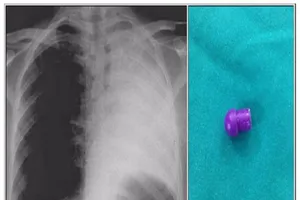

Xẹp phổi trái vì nuốt phải đầu bút bi

Xương cá hình cây dù chui vào phổi

Hóc xương cá tám tháng mà không biết